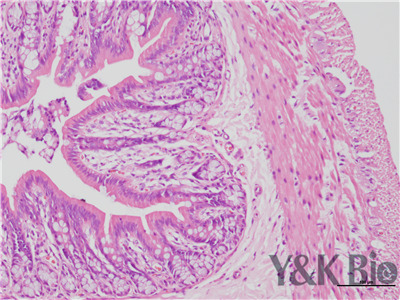

HE染色流程是什么,很多人都不知道,今天跟着小编一起来学习一下,切片的好坏直接影响疾病诊断的及时与准确性。因此一张高质量的HE染色切片,是实验室必须掌握的技术之一。HE染色目前在国内国外病理诊断上被

广泛采用,常规的染色方法。下面一起来看HE染色的基本顺序。一般切片的片子应在60-70度左右的烤箱中烘烤30分钟以才可以进行染色。总的来说是一个时间较长的过程。

1.样品制备

对于贴壁生长细胞,胰酶消化,调整细胞浓度约1×105/ml,滴加于盖玻片上(置于6孔板中),培养相应时间后,取出细胞爬片,用PBS 洗涤3次。2.样品固定 95%乙醇固定20min,PBS洗涤2次,每次1min。3.染核 苏木

素染液染色2-3min,自来水洗涤。4.分色 镜下观察,若细胞核染色过深,用1%盐酸酒精溶液分色数秒,自来水洗涤。 5.染胞质 浸入伊红染液染色1min,自来水洗涤。6.封片 吹干或自然晾干细胞爬片后,黑龙江中性树胶封片。

以上六点就是HE染色的基本步骤,大家可以参考一下哦 。